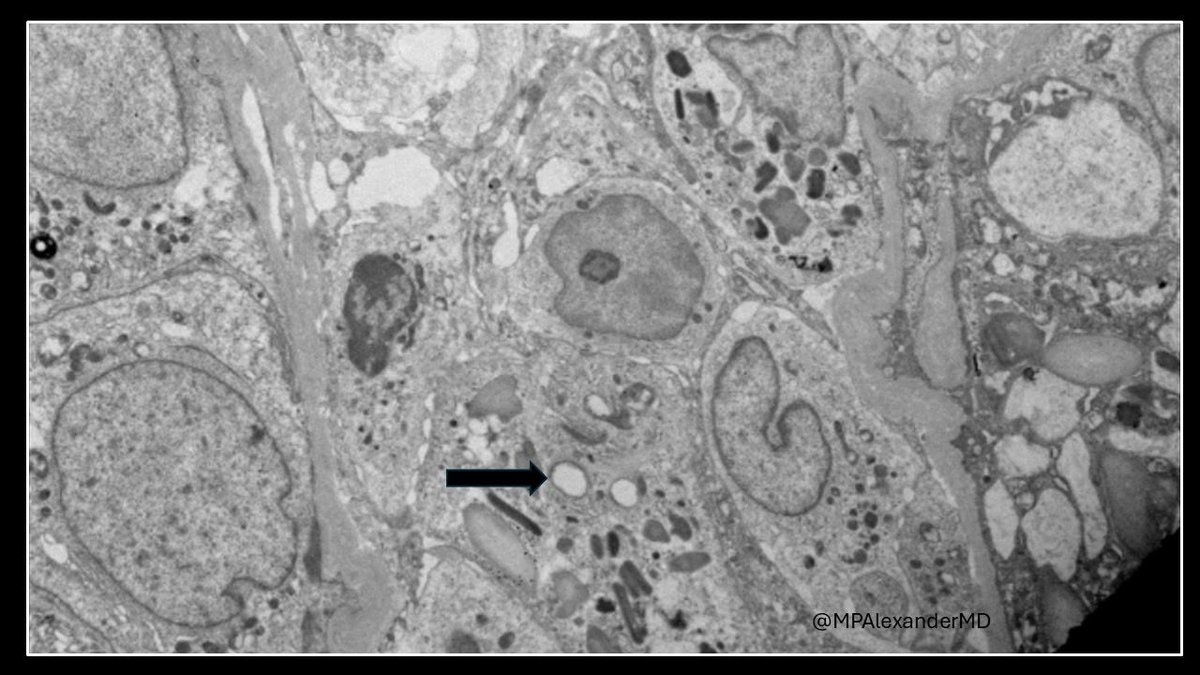

Mini case-series of crystal-storing histiocytosis (CSH) affecting predominantly glomerular loops with detailed literature review of renal CSH, images of one of the cases are depicted below, authors.elsevier.com/c/1Zh4S3uV~y8B…